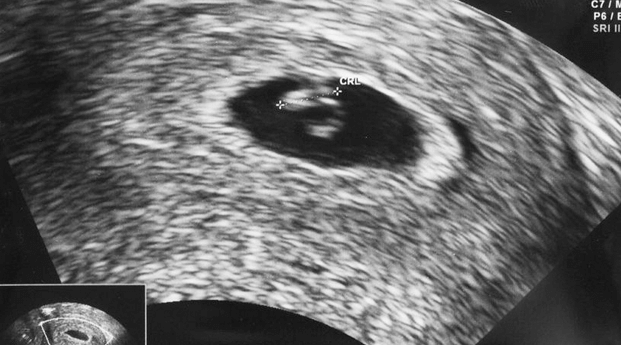

Pemeriksaan ultrasonografi (USG) menjadi cara yang paling akurat dan terpercaya untuk mengetahui usia kehamilan. Butt dan Lim (2014) dalam Journal of Obstetrics and Gynaecology Canada menegaskan bahwa USG di trimester pertama merupakan standar emas (gold standard) dalam dunia kedokteran untuk menentukan usia kehamilan yang paling presisi. Tingkat akurasi USG dapat berbeda tergantung pada usia kehamilan saat pemeriksaan dilakukan. Berikut fokus pengukuran yang biasanya dilakukan dokter:

• Kehamilan di bawah 13 minggu: Dokter mengukur Crown-Rump Length (CRL), yaitu panjang janin dari kepala hingga bokong. Pada fase ini, CRL menjadi metode paling akurat untuk menentukan usia kehamilan dan memperkirakan HPL.

• Kehamilan di atas 20 minggu: Pengukuran berfokus pada Biparietal Diameter (diameter kepala), Abdominal Circumference (lingkar perut), dan Femur Length (panjang tulang paha) untuk menilai pertumbuhan janin secara lebih menyeluruh.

Selain keakuratannya yang tinggi, USG juga memungkinkan dokter mendeteksi sedini mungkin jika terdapat kondisi perkembangan yang memerlukan perhatian khusus. Bagi Ibu dan Ayah, melihat Si Kecil bergerak atau mendengar detak jantungnya melalui layar monitor tentu akan menjadi momen yang sangat membahagiakan.